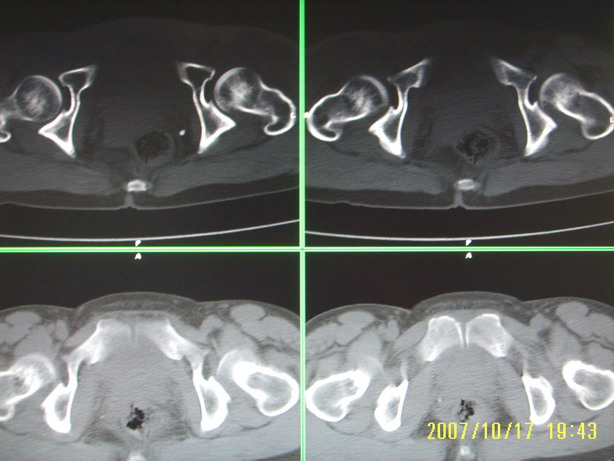

标题: CT10352:女,45岁,股骨头病变,如何诊断?

股骨头病变,如何诊断?

患者女,45岁,左髋部行走疼痛一年,无外伤史,无感染史。x片示囊状骨透亮区

左侧股骨头变形,密度增高,局部塌陷。多考虑:股骨头缺血性坏死伴退变!

左侧股骨头塌陷,其内囊变硬化,骨纹理改变考虑:左侧股骨头坏死及蜕变.

双侧股骨头形态都欠规整,外形欠光滑,尤以左侧明显,考虑双侧髋臼发育不良并退行性变